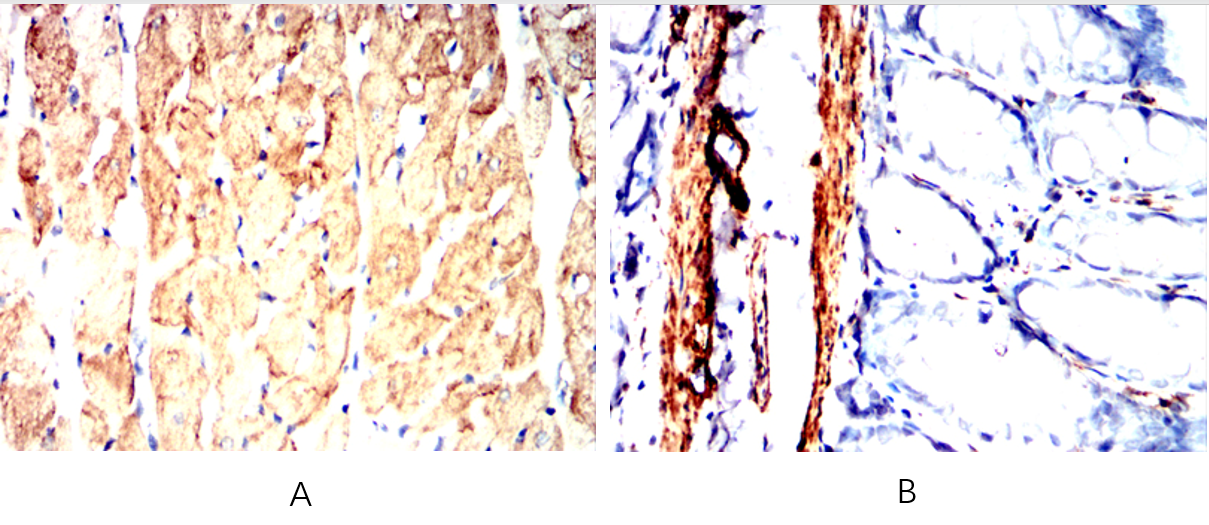

| IHC | IHC:1/100-1/200;IHF:1/50-1/200 | Human,Mouse,Rat |